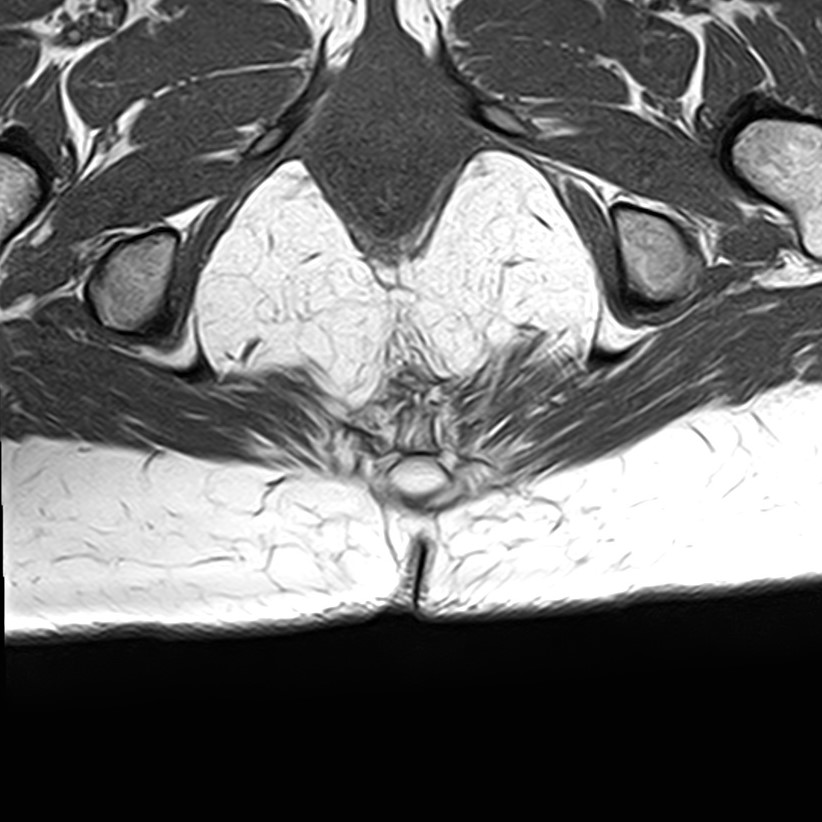

Магнитно-резонансная томография копчика является высокоинформативным методом выявления причин возникновения кокцигодинии. В клинике «Доступная медицина» диагностика осуществляется на новейшем высокопольном томографе закрытого типа TOSHIBA VANTAGE TITAN 1,5 Тесла, обеспечивающем высочайшее качество изображений исследуемой зоны.

Томограф позволяет детально визуализировать как костные структуры копчика, так и окружающие мягкие ткани данной анатомической области, включая мышцы, связки, нервные сплетение, сосуды и прилежащие органы малого таза. МРТ копчика дает возможность диагностировать патологические процессы в самом копчике и выявить их взаимосвязь с патологией окружающих структур.